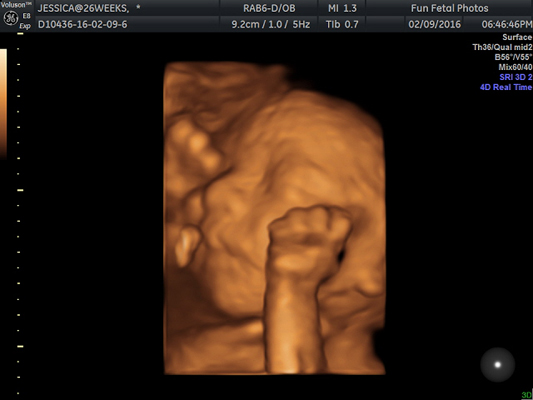

- 401 Fetal Movement Images, Stock Photos & Vectors | Shutterstock

- Fetal Hi-Res Stock Photography And Images - Alamy

- A Full Guide On Interpreting Fetal Movements